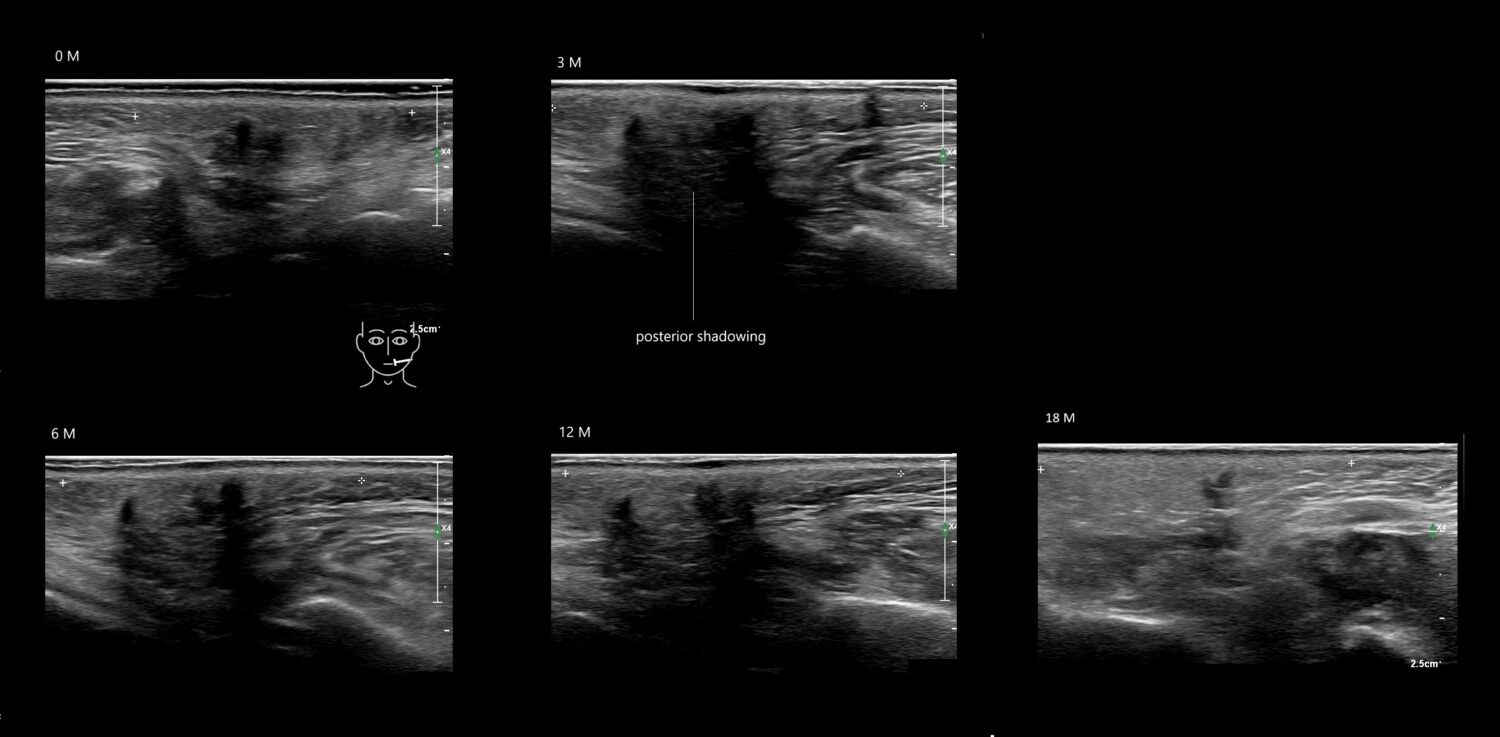

Fillers

Draw in the image on the right where the fillers are located. To check if your answer is correct, please click on the secondary image.

Fillers

Draw in the second image below where the fillers are located. To check if your answer is correct, swipe the first image to the right.